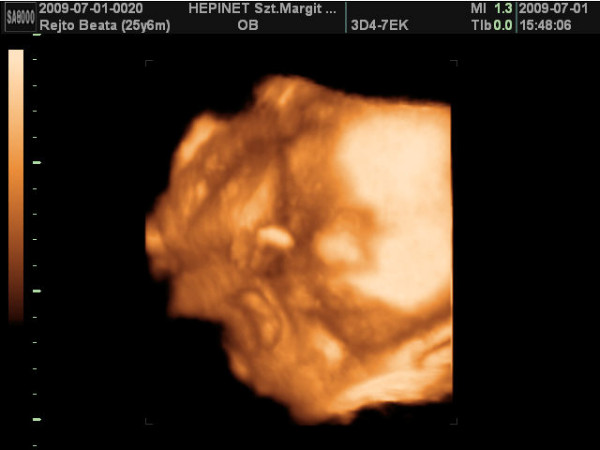

ma vagyok 6 hetes 5 napos.a jó hír,hogy szombaton már láttam és hallottam életemben először a kicsi szívhangját!!!!!!![]()